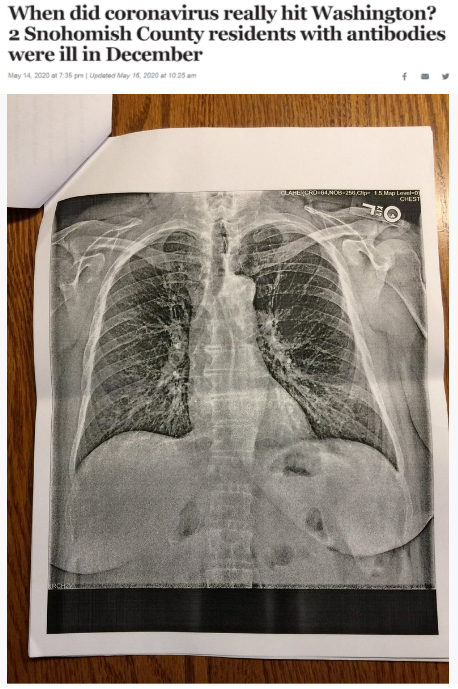

据《西雅图时报》去年5月14日报道,华盛顿州斯诺霍米什县的两位居民在2019年12月出现类似新冠肺炎的症状,之后对他们的新冠病毒抗体检测呈阳性反应。这一结果表明,新冠病毒可能比想象中更早在当地出现。

《西雅图时报》报道截图(题图中的X光片显示其中一位斯诺霍米什县居民的肺部“过度充气”并出现“线性混浊”。医生认为,这可能是叠加上呼吸道肺部感染的表现。)